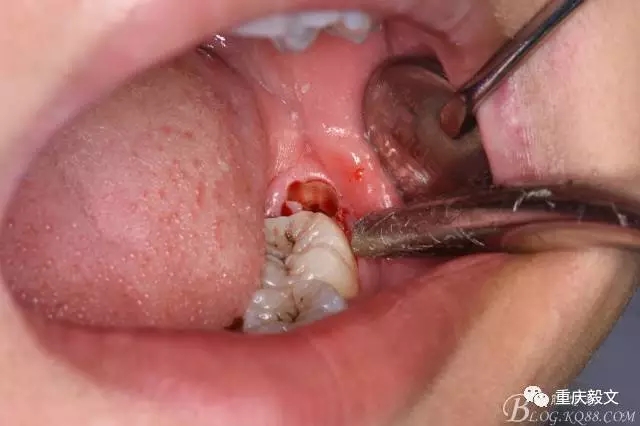

圖5.分離舌側(cè)牙齦

圖6.分離頰側(cè)牙齦,目的使牙冠和牙根能順利從牙齦軟組織脫位。

圖7.高速渦輪鉆分牙

圖8.先從頸部橫斷38